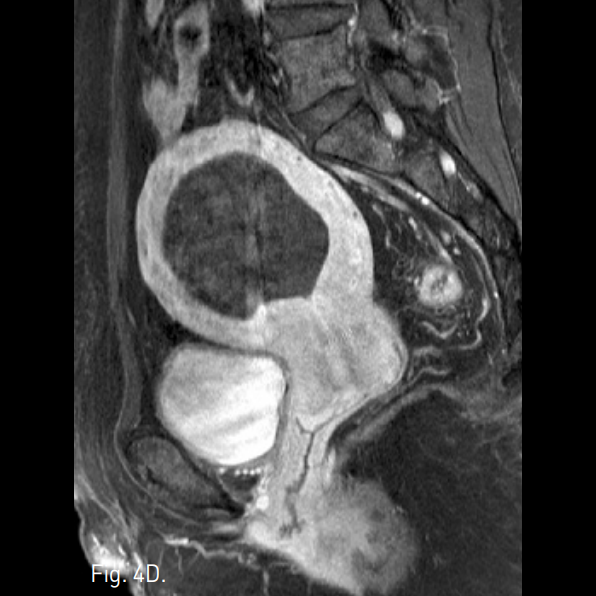

Fig. 4

A-C. Three months follow-up T2-weigh ted transverse (A), coronal (B), sagittal (C) MR images show a huge mass of low signal intensity.

D. Three months follow-up T1-weighted MR image with contrast enhancement shows a non-enhancing uterine mass.

색전술 3개월 후 시행한 MRI에서 자궁근종의 크기가 최대직경 6.0cm에서 5.5cm로 감소하였고, intramural fiber가 모두 괴사된 것을 확인하였다(Fig. 4). 환자는 생리주기가 길어진 것 외에 다른 증상들은 보이지 않다가 약 6개월 후부터 생리주기 때 심한 하복부통과 생리혈의 증가를 호소하였고, endocavitary로 진단되어 자궁소파술을 2차례 시행받았다. 9개월 후 생리주간에 갑자기 덩어리를 동반한 다량의 출혈 경험을 호소하였고, 이후 환자의 생리기간의 증상이 완전히 소실되었다. 자궁동맥색전술 1년 후 추적 검사한 MRI에서 자궁근종 remnant만을 확인할 수 있었다(Fig. 5).